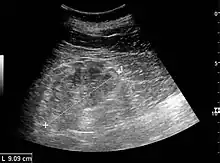

Cortical thickness should be estimated from the base of the pyramid and is generally 7–10 mm. If the pyramids are difficult to differentiate, the parenchymal thickness can be measured instead and should be 15–20 mm (Figure 3). The echogenicity of the cortex decreases with age and is less echogenic than or equal to the liver and spleen at the same depth in individuals older than six months. In neonates and children up to six months of age, the cortex is more echogenic than the liver and spleen when compared at the same depth.[1]

Figure 5. Simple renal cyst with posterior enhancement in an adult kidney. Measurement of kidney length on the US image is illustrated by '+' and a dashed line.[1]